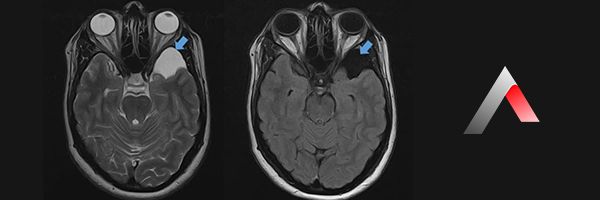

• Manyetik Rezonans Görüntüleme (MRG): MRG, araknoid kistlerin tanısında altın standart olarak kabul edilir. MRG, beyin ve omurilikteki yumuşak dokuların son derece detaylı görüntülerini sağlar ve kistin boyutunu, konumunu, içeriğini ve çevre dokular üzerindeki etkisini açıkça gösterir. Özellikle araknoid kistleri diğer sıvı dolu yapılardan (örneğin epidermoid kistler) ayırt etmek için çok etkilidir.